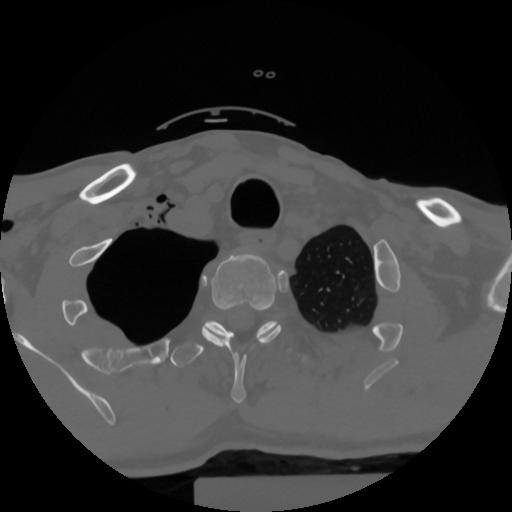

12 P.BLANDAS,,Vol,0.5,P.BLANDAS,,